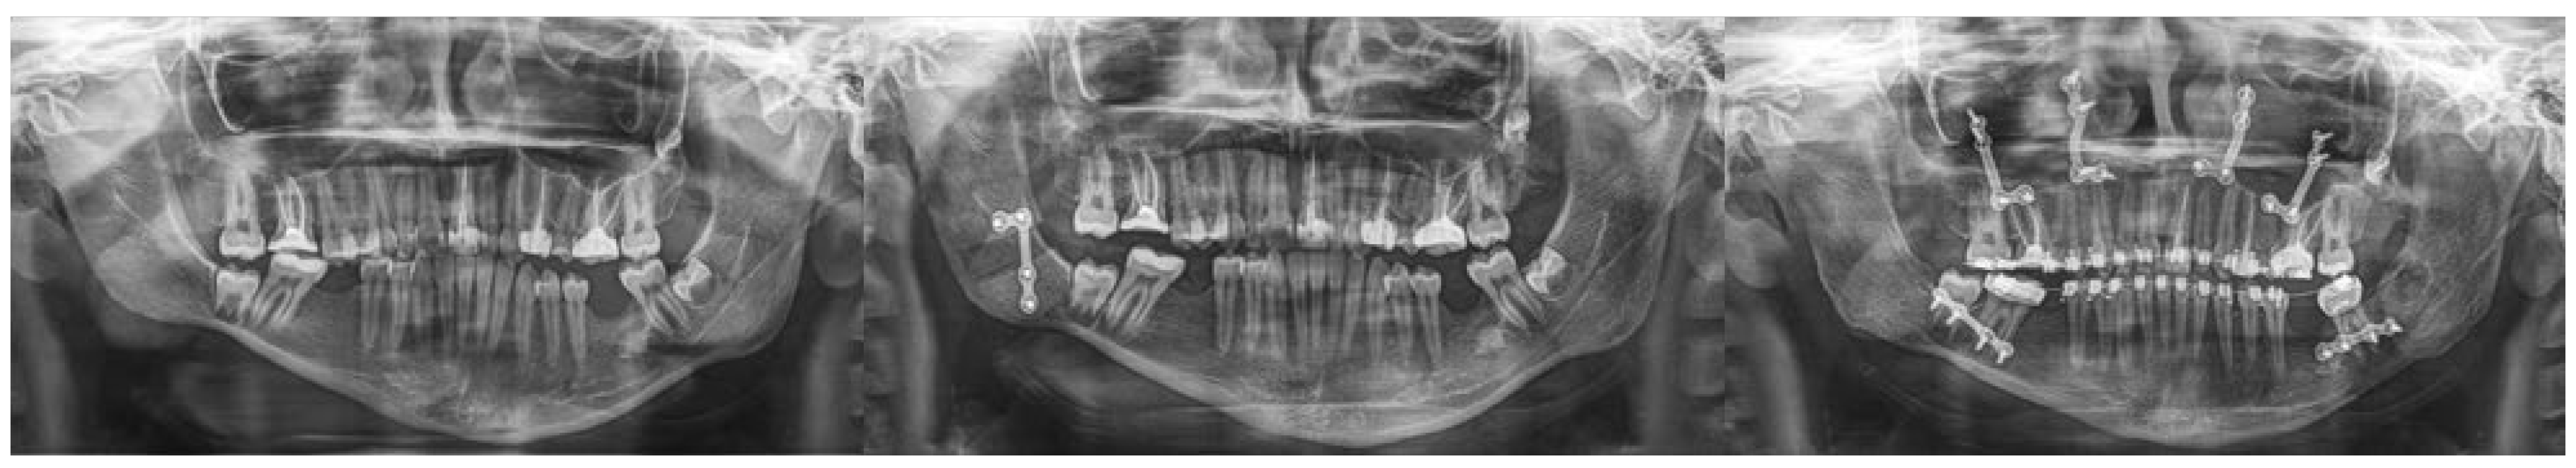

Figure 4. Orthopantomographic radiographs illustrate the preoperative condition, the postoperative situation after sagittal ramus osteotomy and fixation with a L-plate, and the result following the second surgical stage with L-plate removal and subsequent orthognathic correction.

The third case (Figure 3 and Figure 4) concerned a patient with type I hemifacial microsomia, characterized by preservation of the temporomandibular joint, auricular malformation, and involvement of the marginal mandibular branch of the facial nerve. A two-stage treatment was planned. In the first stage, sagittal ramus osteotomy, as described by Obwegeser, was performed, and stabilized with titanium osteosynthesis. Fixation was obtained with a L-plate (2.0 system) fixed with its short arm to the distal segment, allowing for easier removal after consolidation. During this period, orthodontic alignment and leveling of the maxillary arch were carried out. In the second stage, the osteosynthesis material was removed, and definitive orthognathic correction was performed with a bilateral sagittal split osteotomy (Obwegeser–Dal Pont) combined with a Le Fort I osteotomy.

All patients included in this series successfully underwent vertical augmentation of the hypoplastic mandibular ramus, achieving augmentations ranging from 15 to 25 mm (mean: 19.93 mm) on one-year post-operative CT scans, depending on the applied technique. The first approach, consisting of a bidirectional distraction after a full-thickness osteotomy above the lingula, provided satisfactory bone regeneration and correction of mandibular angle inclination, though difficulties in device placement within a limited anatomical space and challenges in vector control were consistently observed. The second technique, employing a unidirectional distractor applied to a sagittal osteotomy of the ramus according to Obwegeser, improved control of the vertical augmentation vector due to the preserved cortical contact and allowed easier fixation and removal of the device. The third approach, based on direct vertical augmentation and rigid fixation of the sagittal osteotomy, eliminated the need for distractors, simplified intraoperative management, and reduced overall treatment costs, while still ensuring reliable consolidation with stable bony contact.